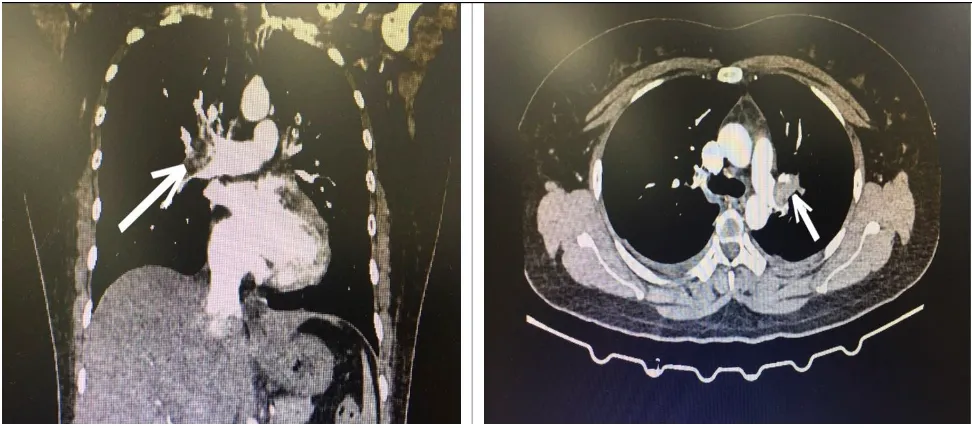

Hình ảnh CT lồng ngực bệnh nhân bị tắc động mạch phổi cấp tính |

Khi vào BV, bệnh nhân được chỉ định xét nghiệm cấp cứu, siêu âm tim có hình ảnh giãn buồng tim phải, hở nặng van ba lá, tăng áp lực động mạch phổi.

Khi đó bác sĩ cấp cứu hướng chẩn đoán tới bệnh thuyên tắc động mạch phổi cấp và quyết định cho chụp CT ngực có tiêm thuốc cản quang, kết quả là hình ảnh huyết khối động mạch phổi 2 bên.